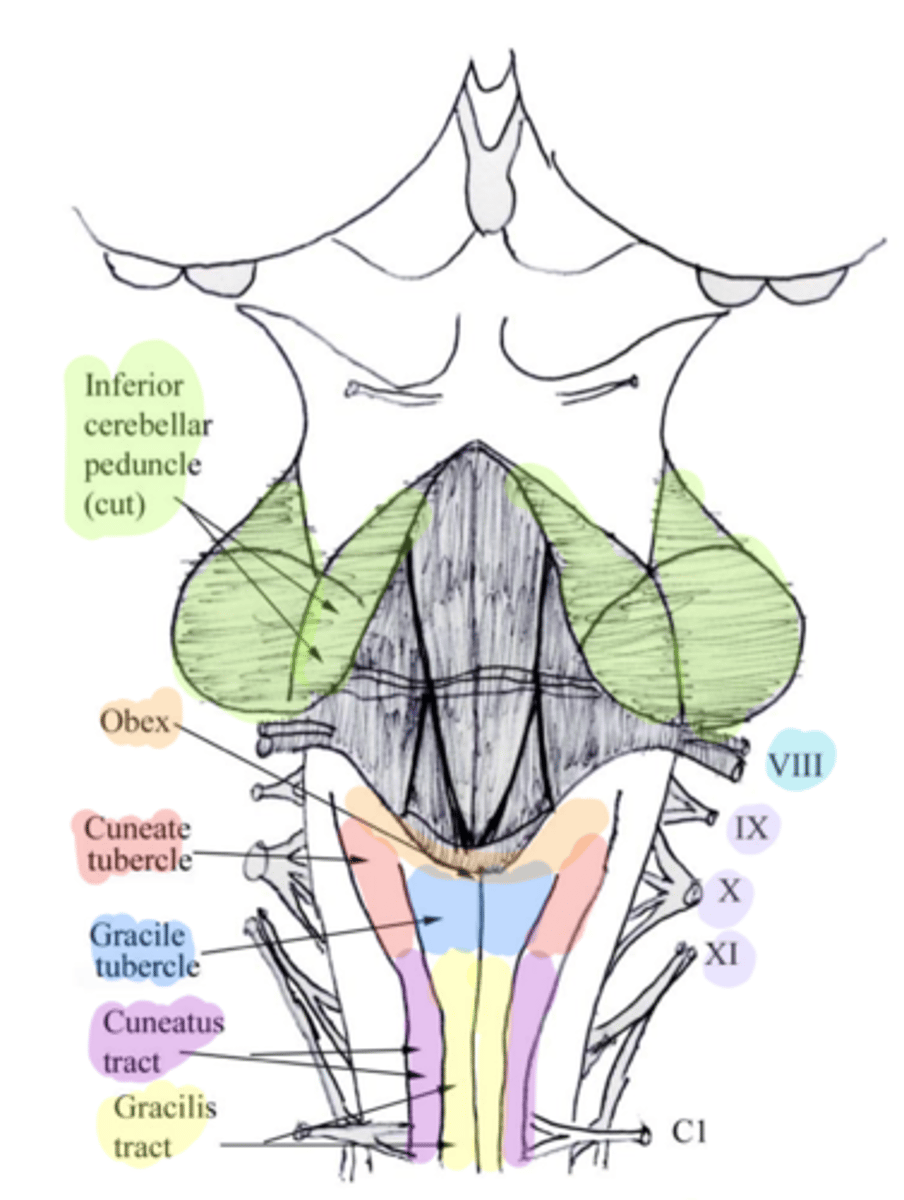

white matter stalks that connect the medulla to the cerebellum

**these help to form the lateral walls of the caudal portion of the 4th ventricle

inferior cerebellar peduncles

medial paired ridges of tissue on the dorsal aspect of the closed portion of the medulla

tractus gracilis

lateral paired ridges of tissue on the dorsal aspect of the closed portion of the medulla

tractus cuneatus

superior ends of the medial paired ridges of tissue on the dorsal aspect of the closed portion of the medulla, formed by namesake nuclei

gracilis tubercles

superior ends of the lateral paired ridges of tissue on the dorsal aspect of the closed portion of the medulla, formed by namesake nuclei

cuneatus tubercles

V-shaped boundary of the caudal aspect of the 4th ventricle that marks the boundary between the open and closed portions of the medulla

obex

name the groove

pontomedullary junction

general portion of the medulla

open medulla

general portion of the medulla

closed medulla

pyramids

ventral median fissure

pyramidal decussation

C

inferior cerebellar peduncles

cuneate tubercle

gracilis tubercle

cuneatus tract

gracilis tract

obex